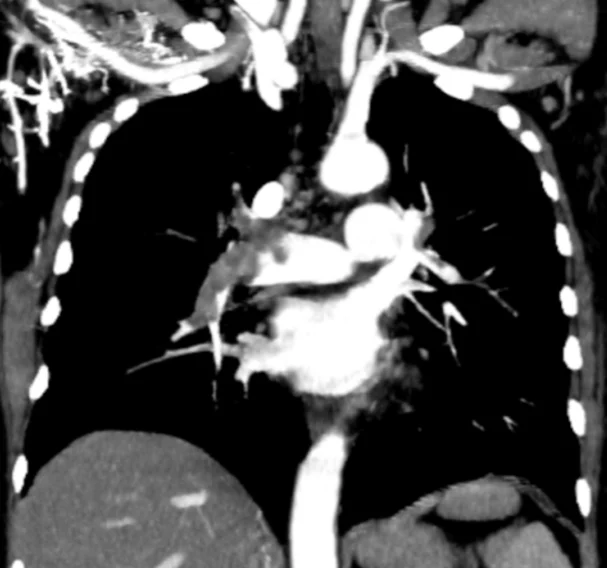

Figure 3. Coronal Contrast – Enhanced CT Pulmonary Angiography (CTPA)

This coronal reformatted contrast – enhanced CT image demonstrates extensive intraluminal filling defects within the central pulmonary arterial system, consistent with acute pulmonary embolism.

Key Radiologic Findings:

- A large hypodense filling defect is visualized within the main pulmonary artery extending into the right and/or left pulmonary arteries.

- The thrombus is surrounded by contrast, clearly delineating the embolus.

- The clot appears to bridge across the pulmonary artery bifurcation, raising suspicion for a:Saddle pulmonary embolism

- There is a partial obstruction of blood flow to both lungs.

- Peripheral pulmonary arterial branches may show reduced opacification.

Clinical Significance:

- This represents a high clot burden pulmonary embolism, which is clinically significant and potentially life – threatening.

- Saddle emboli are associated with: Increased risk of right ventricular failure, higher likelihood of hemodynamic instability

- In the context of prior findings (e.g., subclavian vein thrombosis), this confirms embolic propagation from a proximal venous source.

Diagnostic Contribution:

This image is crucial for:

- Assessing the extent and distribution of emboli

- Identifying central (proximal) embolism, which has a greater clinical impact than peripheral emboli

- Supporting risk stratification and urgent treatment decisions

Radiology Insight (Expert Level):

- Coronal reconstructions are particularly useful for: Visualizing longitudinal clot extent, detecting saddle emboli

- Acute emboli typically: Form central filling defects, expand the vessel

- Chronic emboli (not suggested here) would show: Eccentric wall-adherent thrombusVessel narrowing or webs